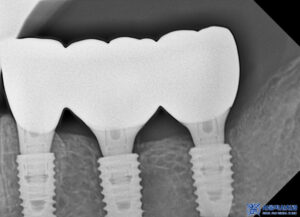

본을 뜬 후 맞춤형 지대주를 제작하고,

그에 맞는 보철물을 제작하여

교합과 형태, 색상까지

세심하게 조정했습니다.

이렇게 정밀하게 작업된 보철물은

자연스러운 느낌을 주며,

환자분의 편안한 씹는 기능을

지원할 수 있도록

설계되었습니다.

치유기간을 기다린 후

위쪽도 본원 원내기공소에서

직접 제작한 개인 맞춤형

임플란트 보철물을

세팅해 드렸습니다.